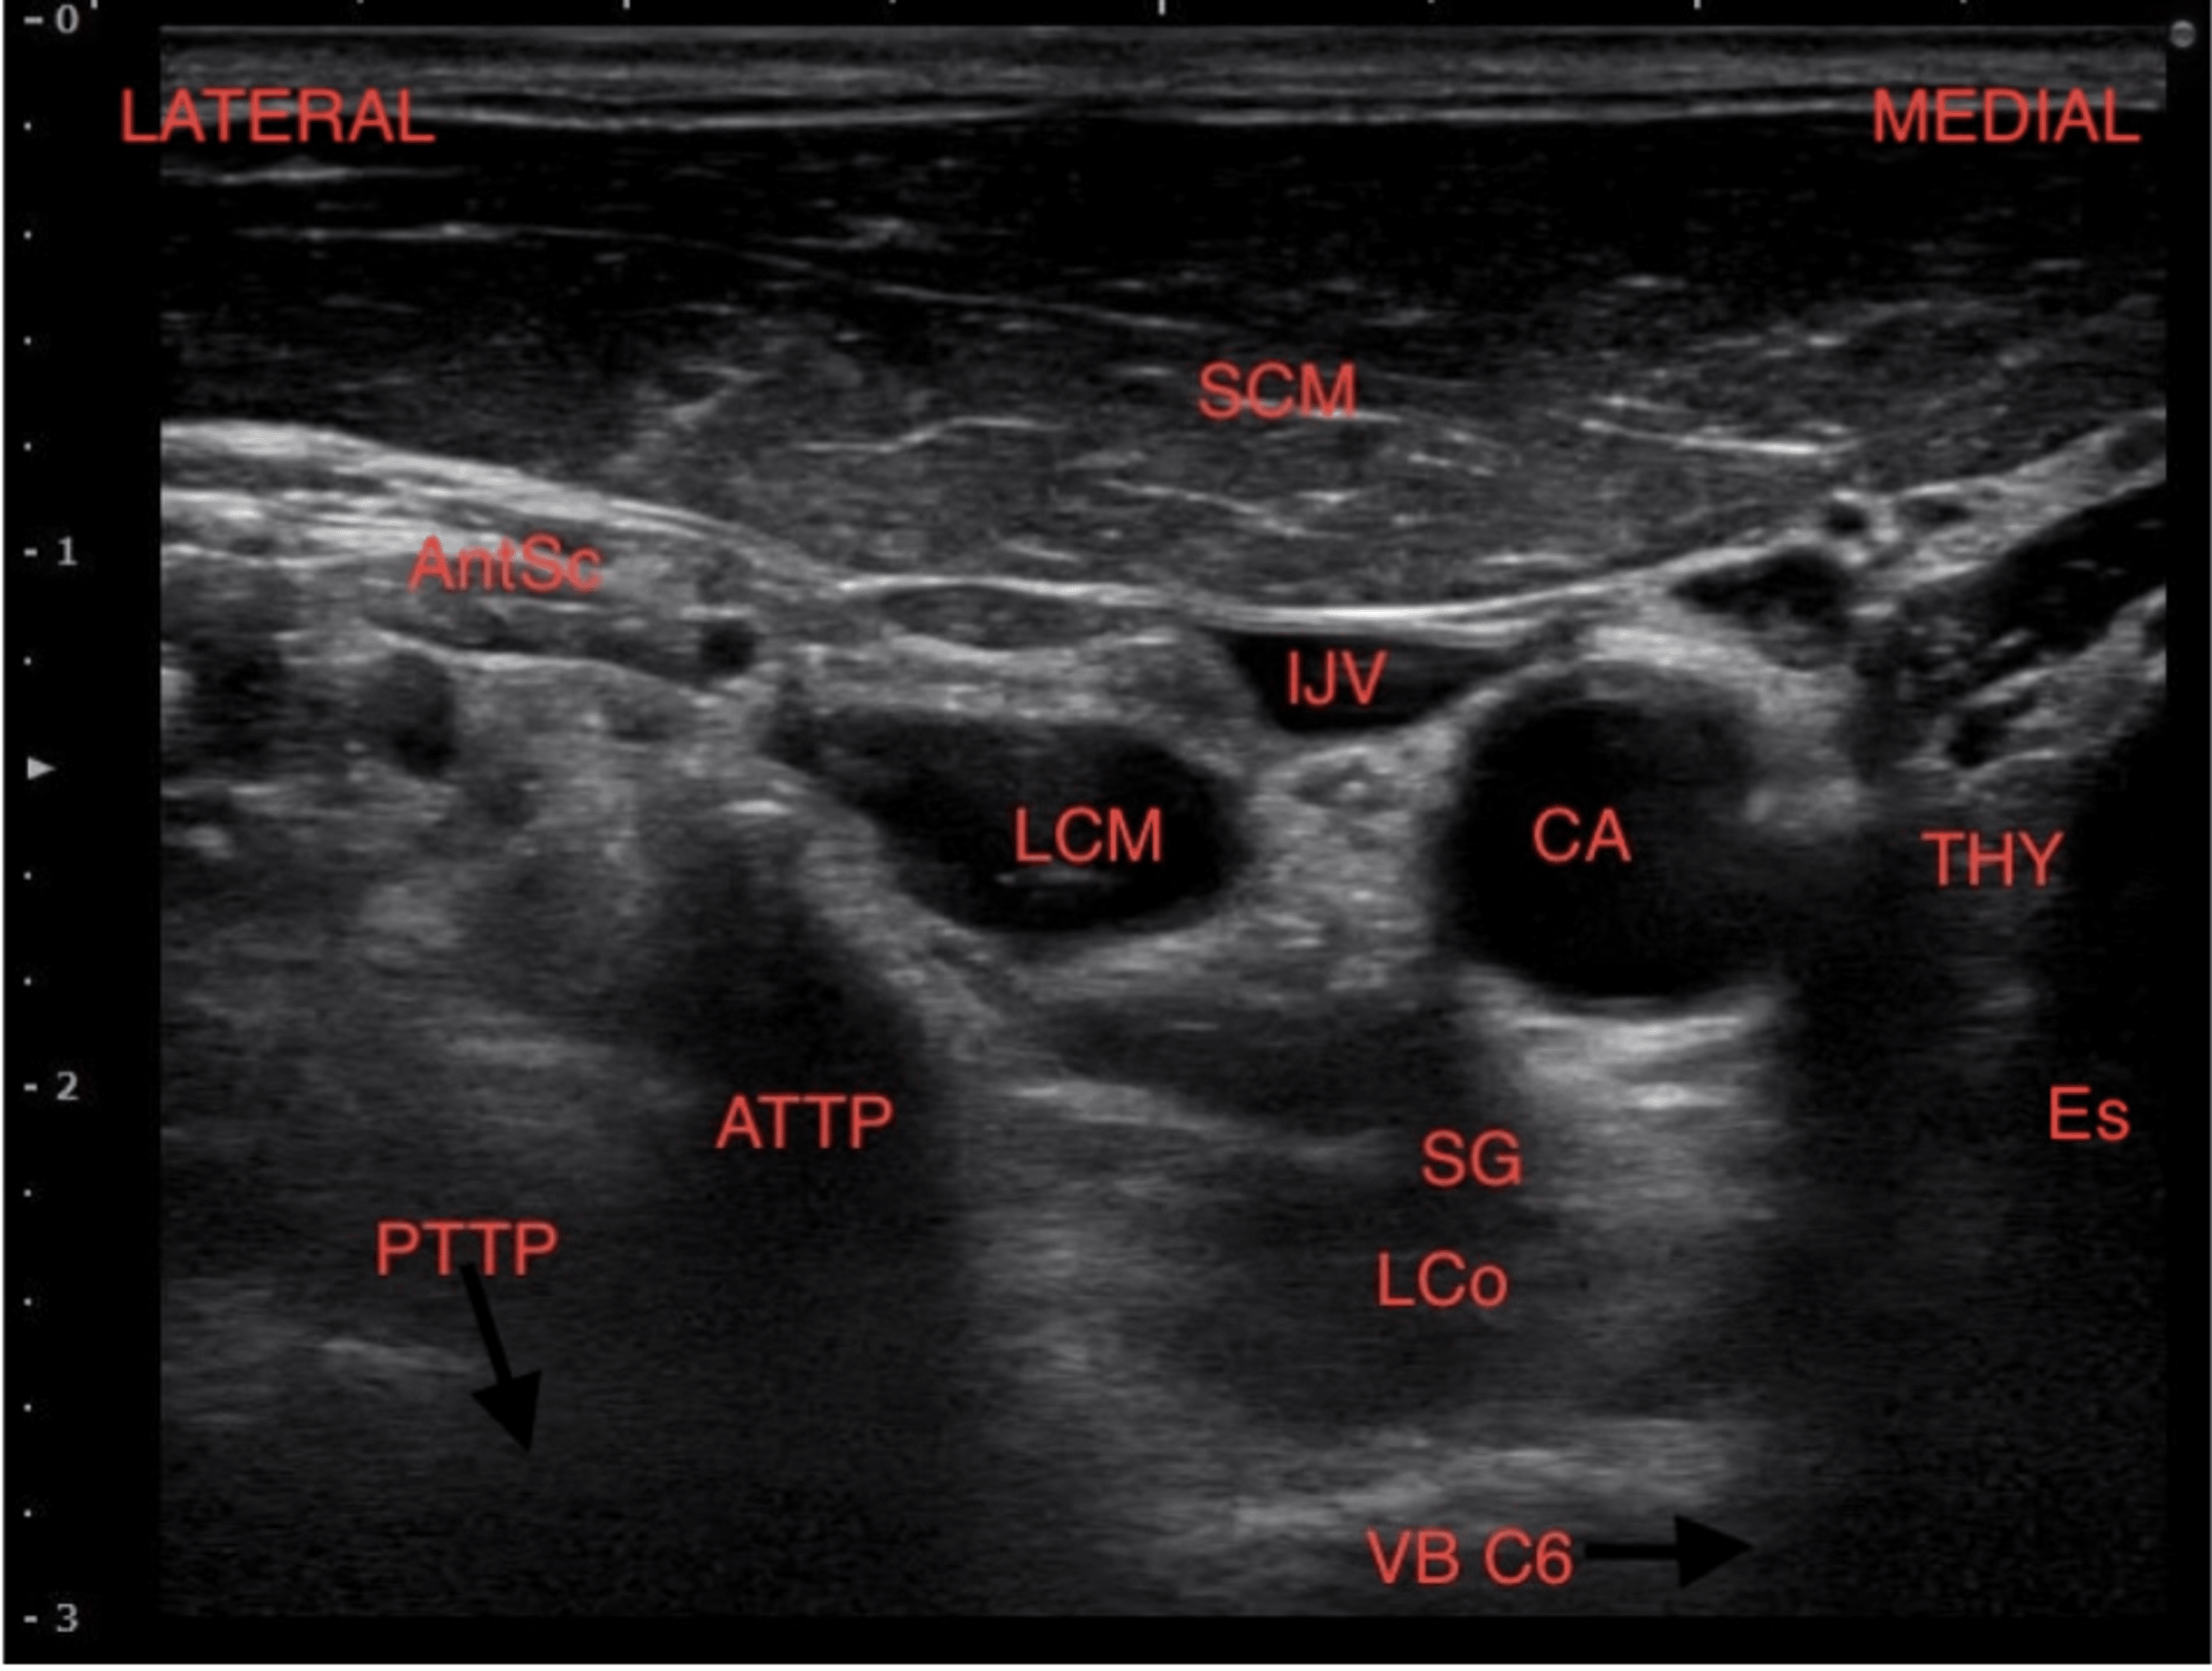

From www.aiophotoz.com

Horizontal Ultrasound Imaging Of The Stellate Ganglion Block Scm What Are Stellate Ganglion Blocks Used For stellate ganglion block (sgb) is a procedure involving the injection of a local anesthetic surrounding the stellate. a stellate ganglion block (sympathetic nerve block) is a localized anesthetic injection used to treat pain,. what is a stellate ganglion block? It is an injection into a group of nerves located in the neck and can be used to. What Are Stellate Ganglion Blocks Used For.